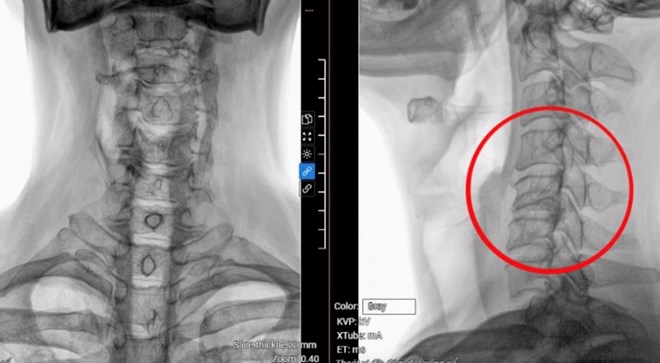

Phim chụp MRI hiển thị vị trí đốt sống cổ bị thoát vị, tổn thương tủy của bệnh nhân. Ảnh: Bệnh viện cung cấp

Kết quả chụp MRI tại Bệnh viện Đa khoa Tâm Anh TPHCM cho thấy bệnh nhân bị thoát vị đĩa đệm nặng từ C3 đến C7, kèm theo gù cột sống cổ và chèn ép tủy ở C5, C6. Thêm vào đó, bệnh nhân cũng bị thoát vị đĩa đệm ở cột sống thắt lưng, gây chèn ép thần kinh khá nặng ở L4, L5.